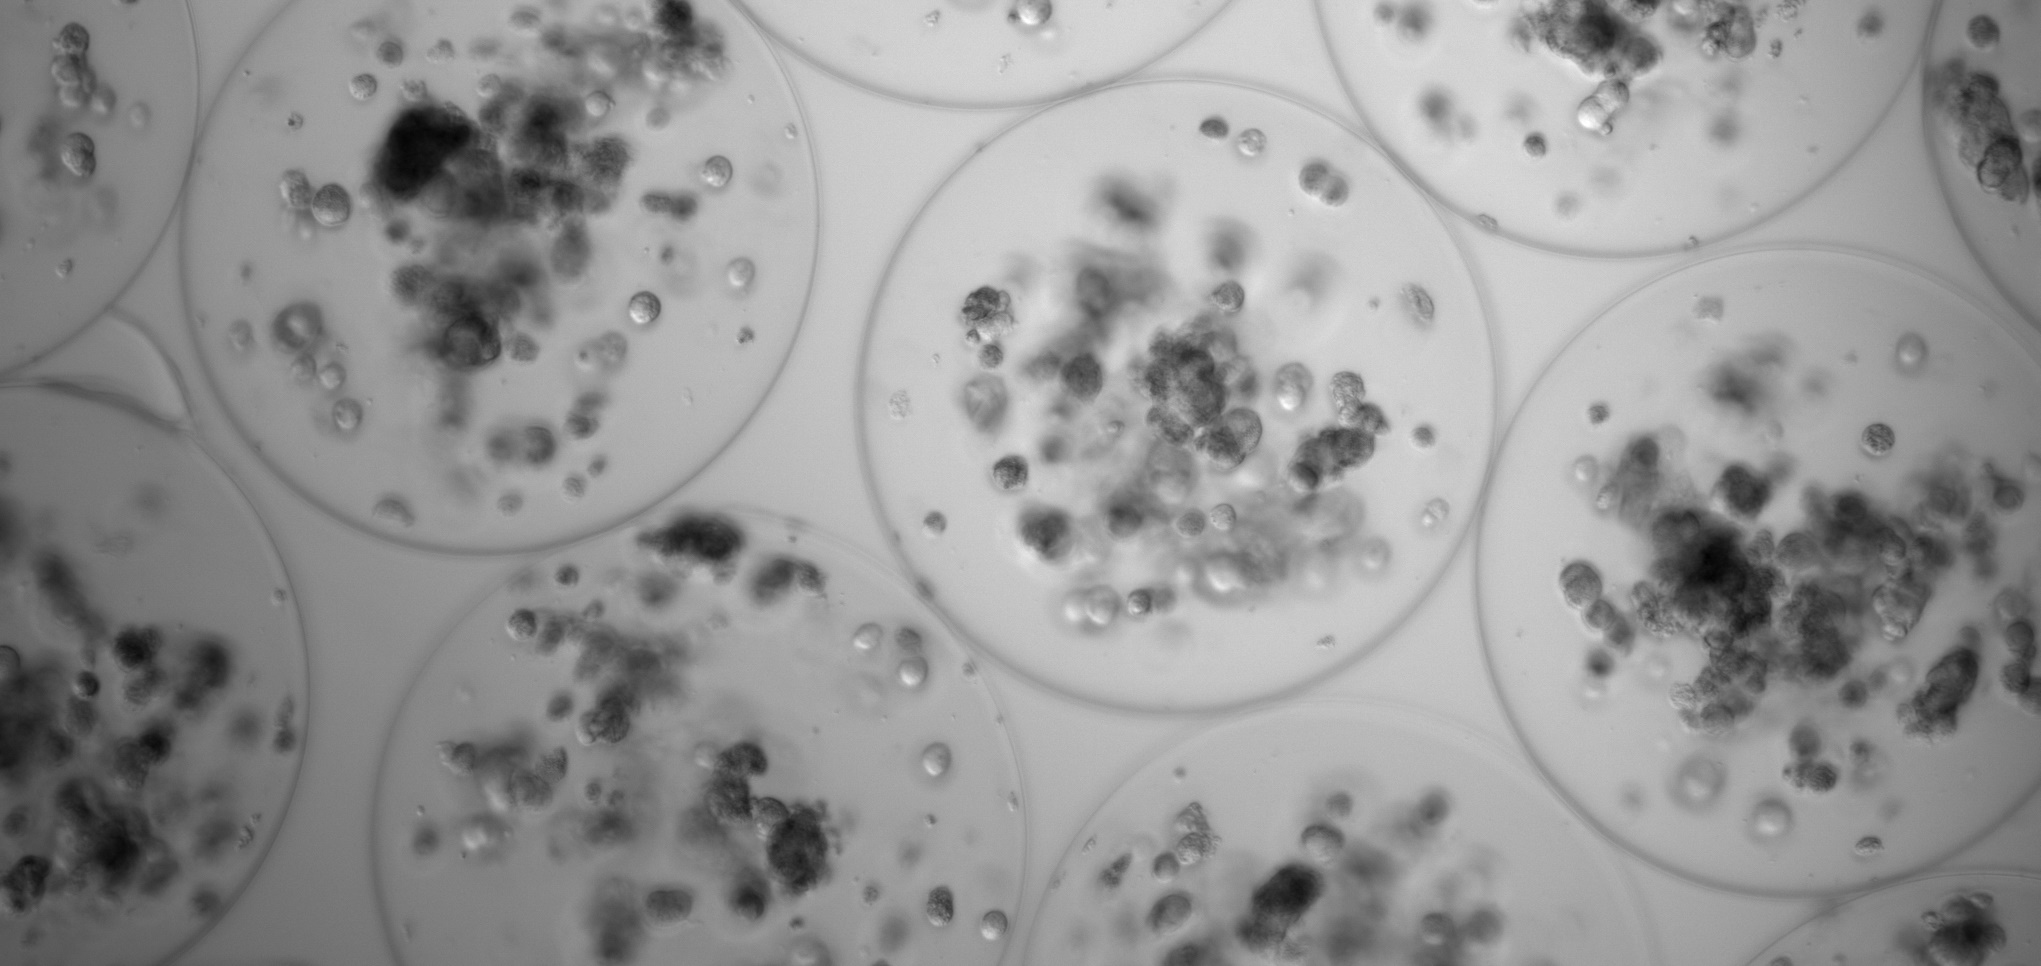

Imagen de cardioesferas microencapsuladas

Desde la Unidad de Formulación de Fármacos de NANBIOSIS se realizaron diferentes acciones como: aislar, expandir y caracterizar células derivadas de cardiosfera (CDC); optimizar las condiciones de encapsulación de CDCs en microcápsulas de alginato; evaluar si las propiedades físicas y químicas de los CDC encapsulados eran adecuadas para el catéter desarrollado en el proyecto; determinar que el perfil de secreción de factores tróficos no cambió en CDC después de la encapsulación; dotar a la Universidad de Zaragoza de las microcápsulas y CDC encapsuladas necesarias para su caracterización mecánica y para evaluar el comportamiento de las cápsulas en el catéter y en los animales del Centro de Cirugía Mínimamente Invasiva de Extremadura (CCMIJU); así como otras colaboraciones que se establecieron con el grupo Fraunhofer EMFT en Alemania y con la empresa española IberHospitex, fabricante de los catéteres.